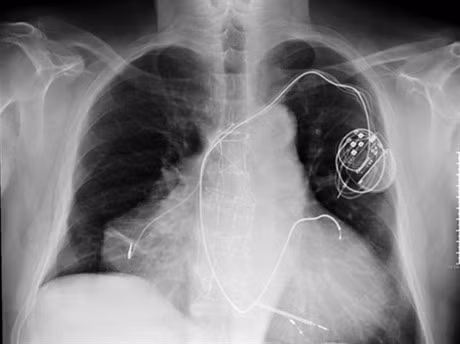

Một nam nhân đến từ San Diego (Mỹ) tên là Tyson Smith đã có một lúc hai nhịp đập từ hai quả tim. Sự việc này là do anh bị bệnh tim bẩm sinh, một ngày nọ anh lên cơn đau tim dữ dội, cơn đau như bóp nghẹt hơi thở của anh, tưởng chừng khó lòng qua khỏi, nhưng rất may anh ta vẫn sống sót.

Khi các bác sĩ kiểm tra họ cho rằng có thể tim đã ngừng đập, nhưng sau khi chụp X-quang đã phát hiện tình trạng bệnh lý khác thường. Sau đó các bác sĩ quyết định ghép cho anh một quả tim phù hợp khác, nó phải kết hợp với trái tim bị bệnh mới giúp anh duy trì sự sống. Và hiện nay anh có hai quả tim đập cùng lúc, Smith hy vọng mình có thể sống thêm 10 năm nữa.